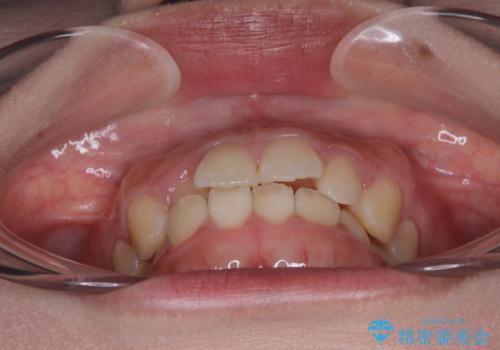

- 前歯のデコボコが気になるでのことで来院された患者様です。

歯列アーチが狭くスペース不足により前歯がデコボコしている状態でした。見た目を改善しつつ、前歯を前方に突出させず、自然な笑顔を目指したいというご希望でした。